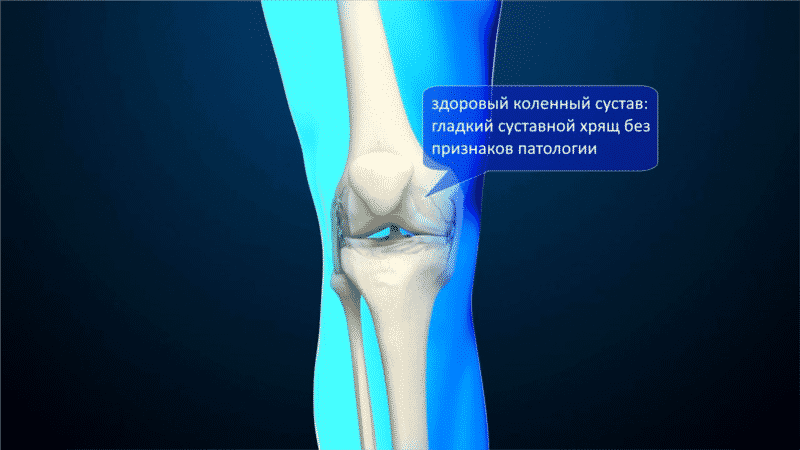

Коленный сустав образован соединением трех костей: бедренной, большеберцовой и надколенником, который чаще называют «коленной чашечкой». Этот сустав наиболее сложен в строении – в процессе сгибания надколенник ложится в специальное углубление, образованное наружным и внутренним выступом бедренной кости.

Поверхности всех трех костей сустава (надколенника, бедренной и большеберцовой костей) покрыты хрящом, благодаря которому обеспечивается процесс скольжения. С внешней стороны сустав ограничен капсулой – синовиальной оболочкой. Жидкость, находящаяся в капсуле, питает и смазывает хрящ, облегчает процесс скольжения, что сохраняет коленный сустав длительное время в здоровом состоянии.

Прочное положение костей относительно друг друга обеспечивают связки коленного сустава, среди которых: передняя крестообразная, задняя крестообразная, внутренняя боковая, наружная боковая связка.